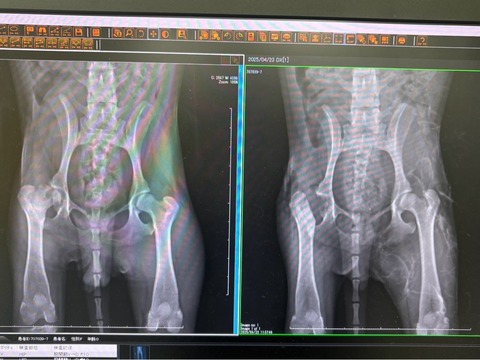

レッグペルテスの モニカちゃん他3匹、

今日ERの八王子にて無事手術が終わりました🙏🌸🙏